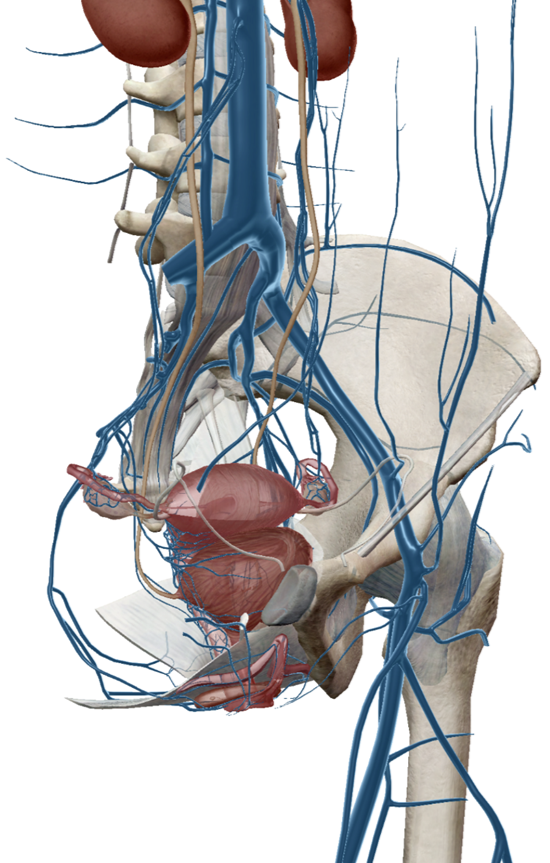

盆腔静脉的解剖

盆腔静脉功能不全/扩张/反流包括髂内静脉和/或性腺静脉(卵巢/精索),以及更为复杂的逃逸点(Escape Points)。这三种盆腔内静脉的解剖特点构成了盆腔静脉功能不全的解剖基础(图1)。盆腔静脉解剖分组一般分为髂静脉系统和会阴静脉系统两大系统以及相应的一些较小的属支:

1、髂静脉系统包括下腔静脉、髂总静脉、髂外静脉和髂内静脉。下腔静脉、髂总静脉、髂外静脉是身体静脉回流的主干道,在国外文献中更多称之为“轴位静脉”。盆腔脏器的静脉多汇入髂内静脉

2、会阴静脉系统引流的主要是生殖器官,包括卵巢/精索静脉、子宫静脉、阴道静脉、会阴深/浅静脉等

3、其他静脉系统包括如腰升静脉、奇/半奇静脉、椎旁静脉丛和腹壁静脉丛等。

图片

图1. 盆腔静脉解剖示意图

盆腔静脉在子宫、卵巢、盆底会阴区域相互沟通。髂内静脉、卵巢静脉返流都会引起盆腔脏器的淤血症状。卵巢静脉返流还会引起腰背部的淤血症状。盆静脉功能不全患者还可能存在会阴或下肢症状,腔静脉反流导致的其他症状与逃逸点是密切相关的。